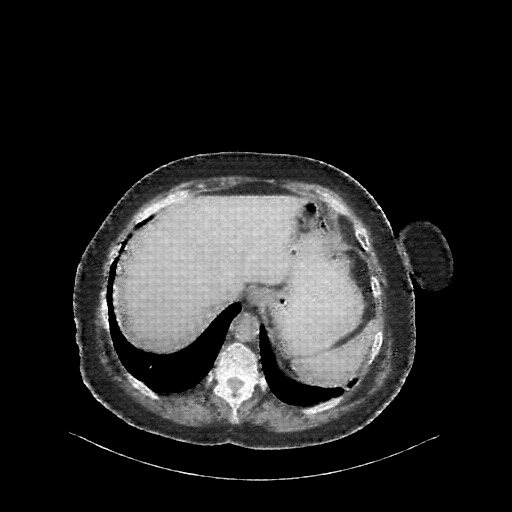

Image Grid

4Γ—3 grid: Rows show different image types (Original NATIVE, Reconstructed NATIVE, Original VENOUS, Generated VENOUS), Columns show windowing techniques (No Window, Lung Window, Mediastinum Window)

Reconstructed NATIVE CT scan (cycle consistency)

Full window (WL 1023.5, WW 4095 β†’ Low βˆ’1024, High +3071)

Lung window (WL -600, WW 1500 β†’ Low βˆ’1350, High +150)

Mediastinum window (WL 40, WW 400 β†’ Low βˆ’160, High +240)